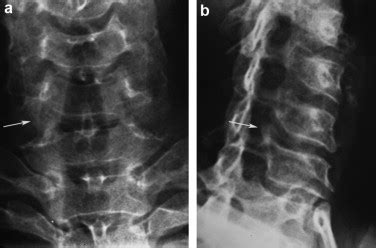

If you’re experiencing neck pain, stiffness, or any neurological symptoms that might suggest uncodiscarthrose, you’ll need to see a doctor for a proper diagnosis. Here’s what to expect during the diagnostic process. It all starts with a physical exam. Your doctor will ask about your symptoms and medical history. They will perform a physical exam to assess your range of motion, check for any tenderness in your neck, and evaluate your reflexes, muscle strength, and sensation in your arms and hands. This will help them to understand the nature and severity of your condition. To confirm the diagnosis and determine the extent of the damage, your doctor will likely order some imaging tests. X-rays can reveal the presence of bone spurs and any narrowing of the disc spaces . They’re a good first step to getting a clear picture of the bone structure. Further examination is possible with MRI (Magnetic Resonance Imaging) or CT scans (Computed Tomography) , which can provide more detailed images of the soft tissues, including the discs, nerves, and spinal cord. MRI is usually the preferred method because it offers the most comprehensive view. CT scans are an option, especially if you can’t have an MRI. Sometimes, additional tests, such as nerve conduction studies (NCS) and electromyography (EMG) , might be necessary to assess nerve function and pinpoint the location and severity of nerve compression. These tests measure the electrical activity in your nerves and muscles. In many cases, it’s a combination of these tests that allows doctors to get a precise diagnosis. Make sure to be open and honest with your doctor about your symptoms. It will help them get a clear idea of what’s going on.

Comprendre les résultats des examens d’imagerie

Interpreting imaging results can be a bit tricky, but here’s a quick guide. X-rays will show any bone spurs or narrowed disc spaces , which are signs of osteoarthritis. The doctor looks for any changes in the bone structure that indicate wear and tear. MRI and CT scans provide more detailed views of the soft tissues. You’ll see the condition of the discs, any nerve compression, and the overall health of the spinal cord. The radiologist (the specialist who reads the scans) will look for: Discs that are bulging or herniated, which means they’re pressing on the nerves. Narrowing of the spinal canal (spinal stenosis), which compresses the spinal cord and nerve roots. Bone spurs (osteophytes) that are putting pressure on the nerves. The report will explain the findings, and your doctor will translate them into a diagnosis that you can understand. The images give the doctor a good idea of what’s going on, and the report will outline the specific issues, helping your doctor create a plan. Always remember to ask your doctor to explain the results in a way that you can easily understand, so you know exactly what is happening in your body. Don’t hesitate to ask questions; it’s your health, after all!